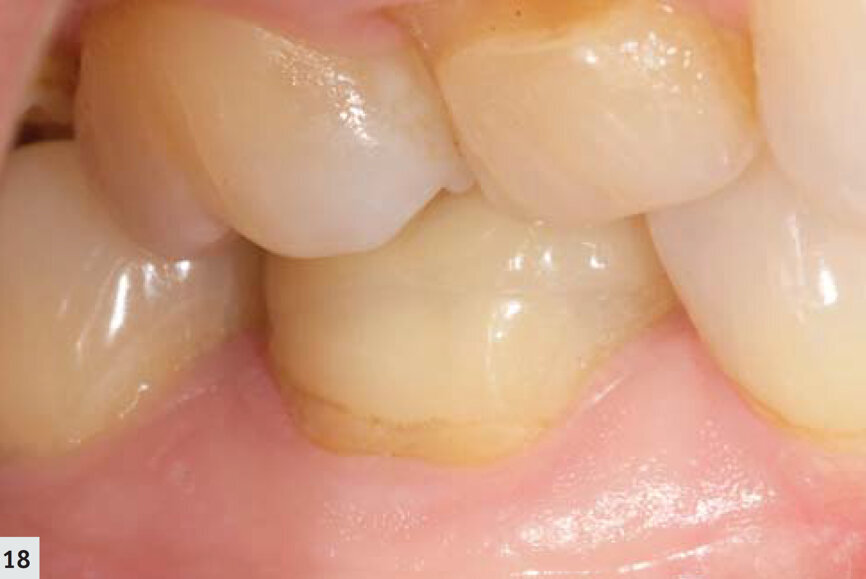

Fig. 18 : Suivi de l’onlay en disilicate de lithium, trois ans après sa mise en place.

La majorité des résines composites émettent une hyperfluorescence sous le rayonnement proche-UV.6, 7 Les autres restaurations, minimes, peuvent facilement être observées en mode détection (Fig. 14). De cette façon, il est possible de déceler la présence d’un surplomb et de définir plus aisément les espaces marginaux (Fig. 15). L’élimination des restaurations défectueuses devient ainsi beaucoup plus facile et s’effectue sans retrait inutile de tissu dentaire sain. De plus, ce mode représente un outil très utile au cours des techniques de scellement ; les excès de ciment résine sont immédiatement détectés et peuvent donc être éliminés (Fig. 16) sans polymérisation simultanée ; après le nettoyage, le même dispositif peut être utilisé pour polymériser les limites marginales (Fig. 17). Au cours du suivi, les restaurations sont mieux visualisées (Figs. 18–19) et il est possible d’examiner rapidement et complètement leurs limites marginales.